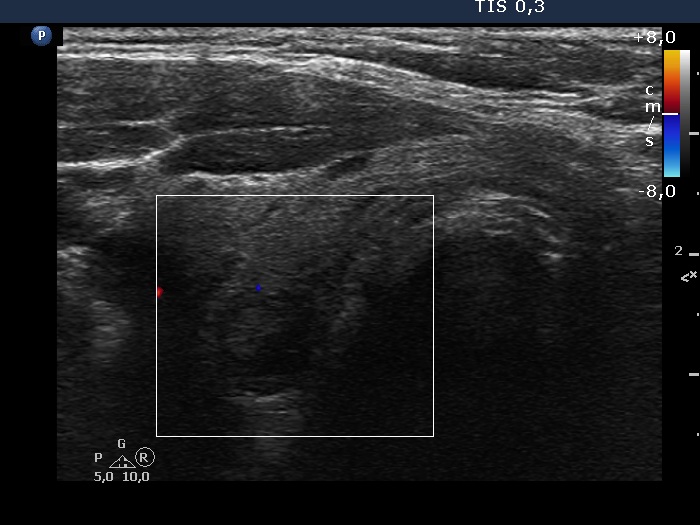

Right lobe, transverse view, color Doppler mode. The lobe is avascular.